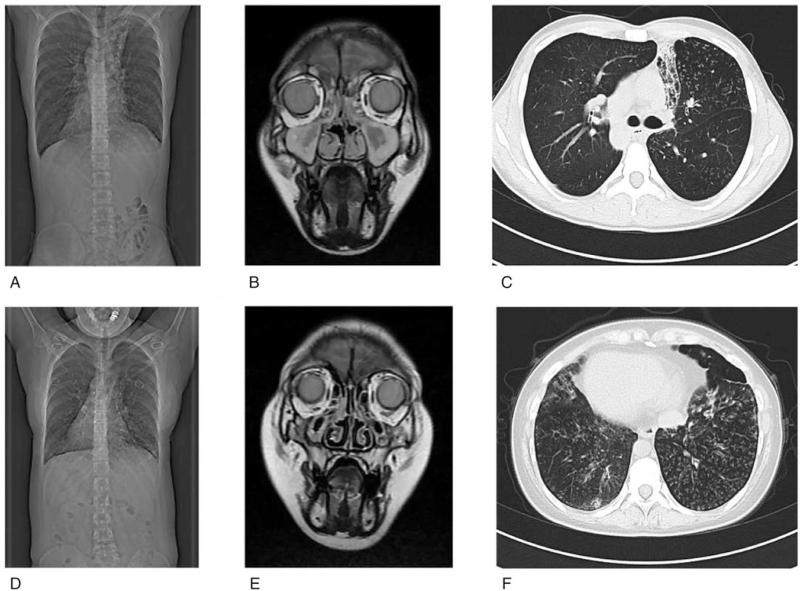

Imaging examination was used to exclude pulmonary inflammation and visceral translocation. Semen analysis was used to assess the quality of the proband's sperm. Transmission electron microscopy (TEM) was conducted to assess the ultrastructure of flagella and cilia. Targeted next generation sequencing and Sanger sequencing and qPCR (real-time quantitative polymerase chain reaction detecting system) were applied to identified mutation of Chinese Family suspected of having PCD. Viable sperm were selected by hypo-osmotic swelling test (HOST) for ICSI.

We report 2 novel mutations in CCDC40 gene (c.1259delA and EX17_20 deletion) resulted in immobility of sperm and infertility of the proband. These mutations were confirmed in the proband's sister (heterozygous) and his parents (recessive carrier) by Sanger sequencing and qPCR. All the spermatozoa from the proband were immotile. Ultrastructural defects were found in flagella and cilia of proband and his sister. Viable sperms were selected by HOST for ICSI and fertilized 9 of 21 eggs. Two frozen embryos were transplanted and a healthy 3500 g boy was delivered at 40 + 4 weeks' gestation. And then, we summarized the genes related to PCD and the mutant sites of CCDC40 gene.